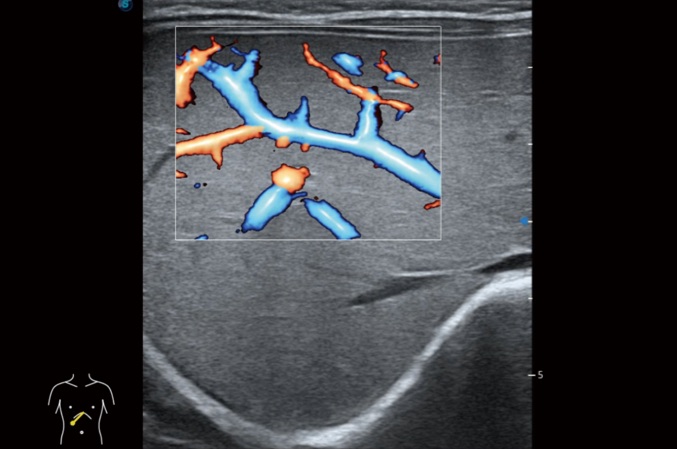

高分辨率血流成像技術(shù)提高了對(duì)低速血流信號(hào)的檢測(cè)能力。在提高空間分辨率的同時(shí),也克服了血流外溢現(xiàn)象,為用戶(hù)提供更加真實(shí)的血流動(dòng)力學(xué)信息。

心血管應(yīng)用